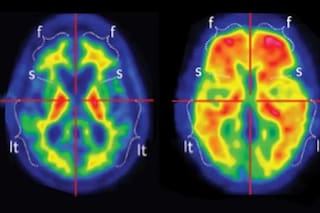

Alarmante. Las devastadoras revelaciones que dejó el escáner cerebral del paciente más joven con Alzheimer